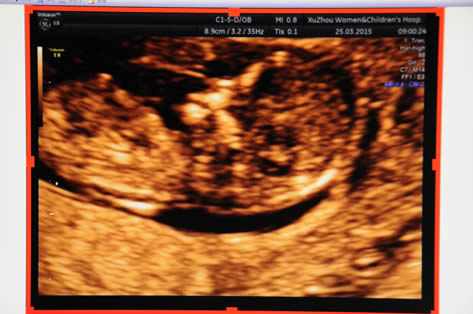

產科:早孕(yùn)期NT、普通產科、係統(tǒng)超聲(四維)、針對性產前超聲、單項產科等;

為滿足臨床需要,配設婦科、產科床旁超聲檢查、術中超聲引導,實施24小時急診檢查。特別在婦科、產科及小兒顱腦、小兒(ér)髖關節疾病的超聲診斷方麵,科室(shì)積累了豐富的經驗,能夠做到快捷、準確,贏(yíng)得了廣大患者的信任,吸引了全市及周邊地區病人前來會診。